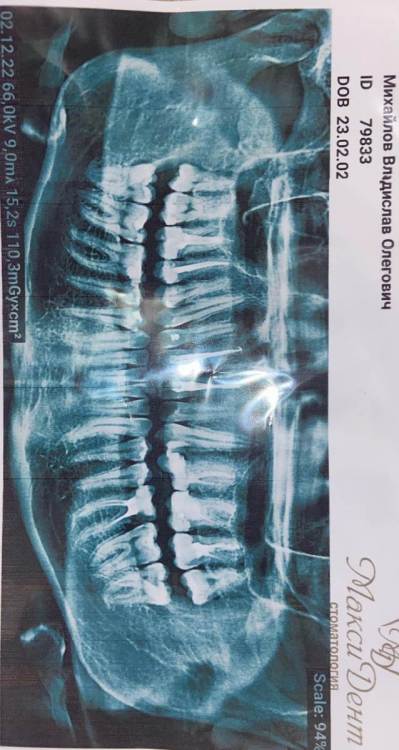

logo5ed Опубликовано 2 декабря, 2022 Поделиться Опубликовано 2 декабря, 2022 Болит зуб 26 в соответствии схеме, уже 4 день мучаюсь боль ноющая, переходящая на 2 соседних зуба. Одиночный рентген зуба у стоматолога нареканий не вызвал. Неужели абсцесс? Ссылка на комментарий

Женька Опубликовано 3 декабря, 2022 Поделиться Опубликовано 3 декабря, 2022 Здравствуйте, по данному снимку действительно сказать что-то очень сложно. Вполне возможно, что пища забилась под нависающие края пломбы на 2.6 зубе. Надо больше данных И в идеале срезы КЛКТ. 1 Ссылка на комментарий

IvanK Опубликовано 5 декабря, 2022 Поделиться Опубликовано 5 декабря, 2022 Здравствуйте Спасибо за разминку шеи)) Удобнее анализировать по правильно расположенной фотографии) К сожалению, без очного осмотра и компьютерной томографии сложно ответить на Ваши вопросы 03.12.2022 в 22:39, Женька сказал: Здравствуйте, по данному снимку действительно сказать что-то очень сложно. Вполне возможно, что пища забилась под нависающие края пломбы на 2.6 зубе. Надо больше данных И в идеале срезы КЛКТ. + 1 1 Ссылка на комментарий